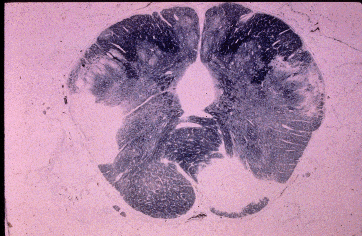

Pathology Images